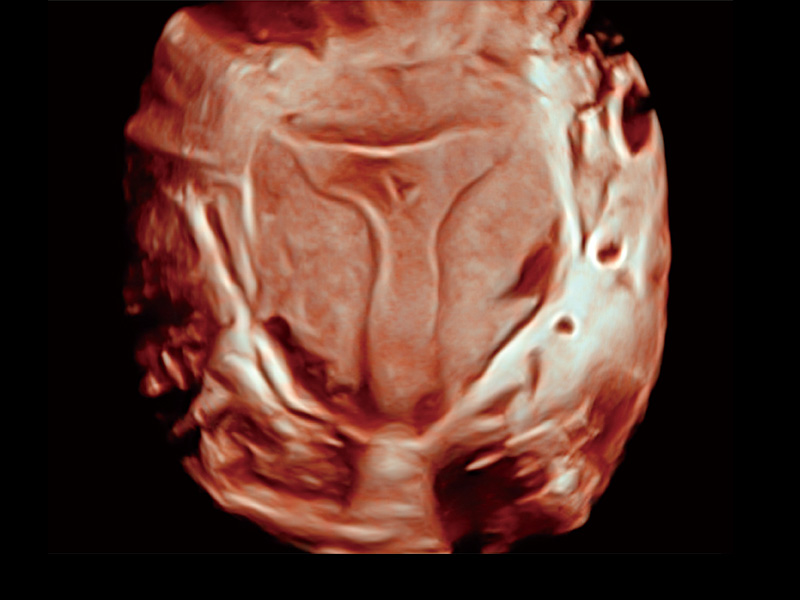

腔内容积探头

腔内三维成像技术获得显著提升,超大扇角在满足日常基础扫查的同时,支持卵泡自动测量及多种三维渲染模式,为您提供更多的诊断信息,尤其是在子宫畸形的诊断,内膜及肿瘤占位观测中起到了重要的作用。

中央型宫腔粘连

单角子宫